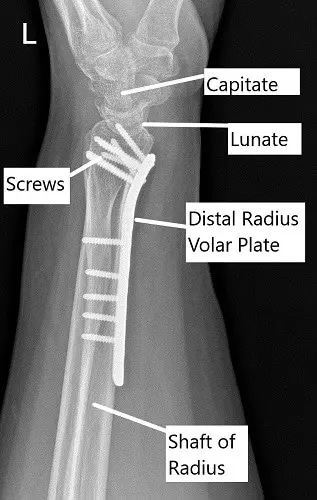

Post-operative x-ray of the wrist in lateral view.

A 5-hole distal radius plate was put and held with a radial olive wire. AP and lateral views were checked and found to be satisfactory. Provisional fixation of the plate was done with a cortical screw oblong hole. Fixation of the plate to the proximal radius was done with a nonlocking screw. Again, checking the reduction to be acceptable, the distal plate was fixed to the distal end of the radius.

A 26 mm cortical nonlocking screw was used to pull the plate to the bone. This screw was later removed and exchanged for a locking screw. The distal fixation was done using multiple locking screws. A proximal fixation of the radius was done using a combination of locking and non-locking screws. The final fixation was checked under C-arm and found to be acceptable.